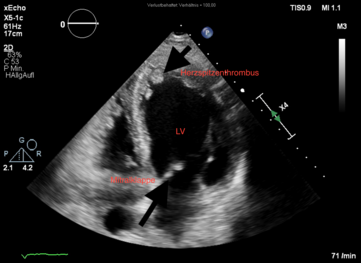

Die Ultraschalldiagnostik, in der Kardiologie Echokardiographie stellt neben dem EKG eine wichtige nicht-invasive Untersuchungsmethode bei der Abklärung von Herzerkrankungen dar. Die Echtzeitbilder des Herzultraschalls zeigen Veränderungen und Defekte des Herzmuskels, der Herzkammern, des Klappenapparates und der zu- und abfließenden Gefäße.

Durch die Echokardiographie lassen sich geschädigte Muskelabschnitte des Herzens nach einem Herzinfarkt, bei Menschen mit koronarer Herzkrankheit (KHK) oder eine Herzmuskelentzündung genauer bestimmen.

Zu den Standartverfahren zur Diagnostik von Herzerkrankungen gehört die transthorakale Echokardiographie (TTE). Dabei legt der Untersuchende den Ultraschallkopf auf definierte Areale der Brustwand und kann so Unregelmäßigkeiten sehen. Sie ist vergleichbar mit einem herkömmlichen Ultraschall. Zusätzliche Informationen ergeben sich durch die Hinzunahme von Doppler- und Farbdopplerdarstellungen. Durch das Messen der Strömungsgeschwindigkeit und das Nachweisen der Strömungsbeschleunigungen wird die Funktion/Dichtigkeit der Herzklappen kontrolliert.

Die Methode der transösophagealen Echokardiographie (TEE) wird umgangssprachlich auch Schluckecho genannt, da ein flexibler Schlauch – ähnlich wie bei einer Magenspiegelung – über den Mund in die Speiseröhre eingeführt wird. Um einen eventuell aufkommenden Würgereiz zu vermeiden, wird ein lokales Betäubungsmittel in den Rachen gesprüht. In vielen Fällen werden auch sedierende Medikamente verabreicht.

An der Spitze des Schlauchs befindet sich eine Ultraschallsonde. Die

Sonde wird bis in die Speiseröhre vorgeschoben. Die Nähe der Speiseröhre zum

Herzen ermöglicht deutlichere Aufnahmen (zum Beispiel des linken Vorhofs oder

etwaiger Blutgerinnselbildungen bei Herzrhythmusstörungen). Auch

angeborene Herzfehler können

durch die transösophageale Echokardiographie genauer Quantifiziert werden.